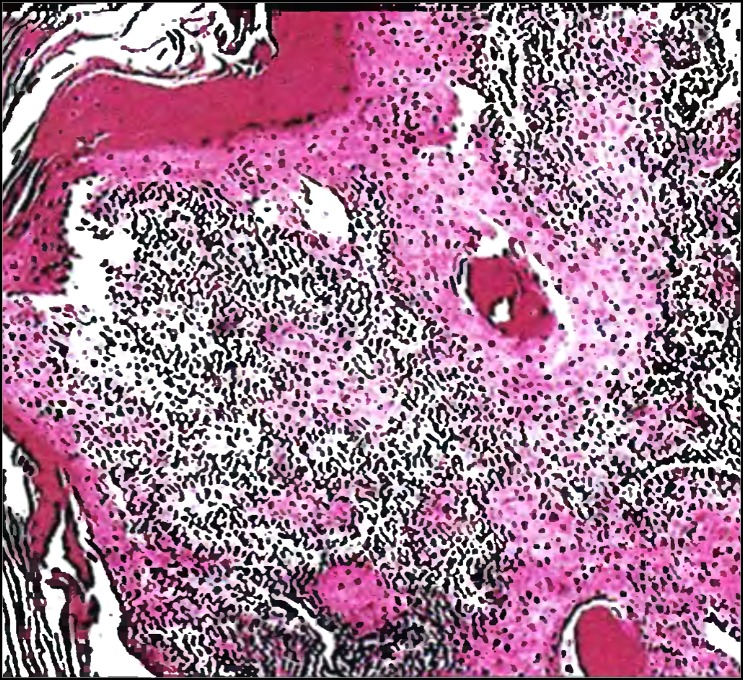

Гистологическое исследование

В соответствии с гистологическим строением в 98% случаев рак гортани представлен неороговевающим или ороговевающим плоскоклеточным эпителием. Реже диагностируется аденокарцинома. В крайне редких случаях (0,4%) – саркома.

Плоскоклеточный высокодифференцированный рак